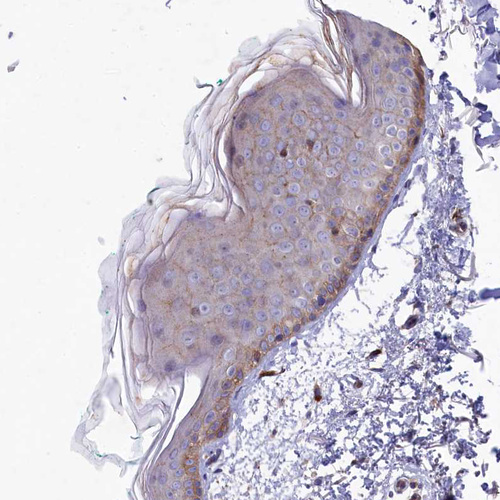

Immunohistochemical staining of human skeletal muscle shows strong cytoplasmic positivity in myocytes.